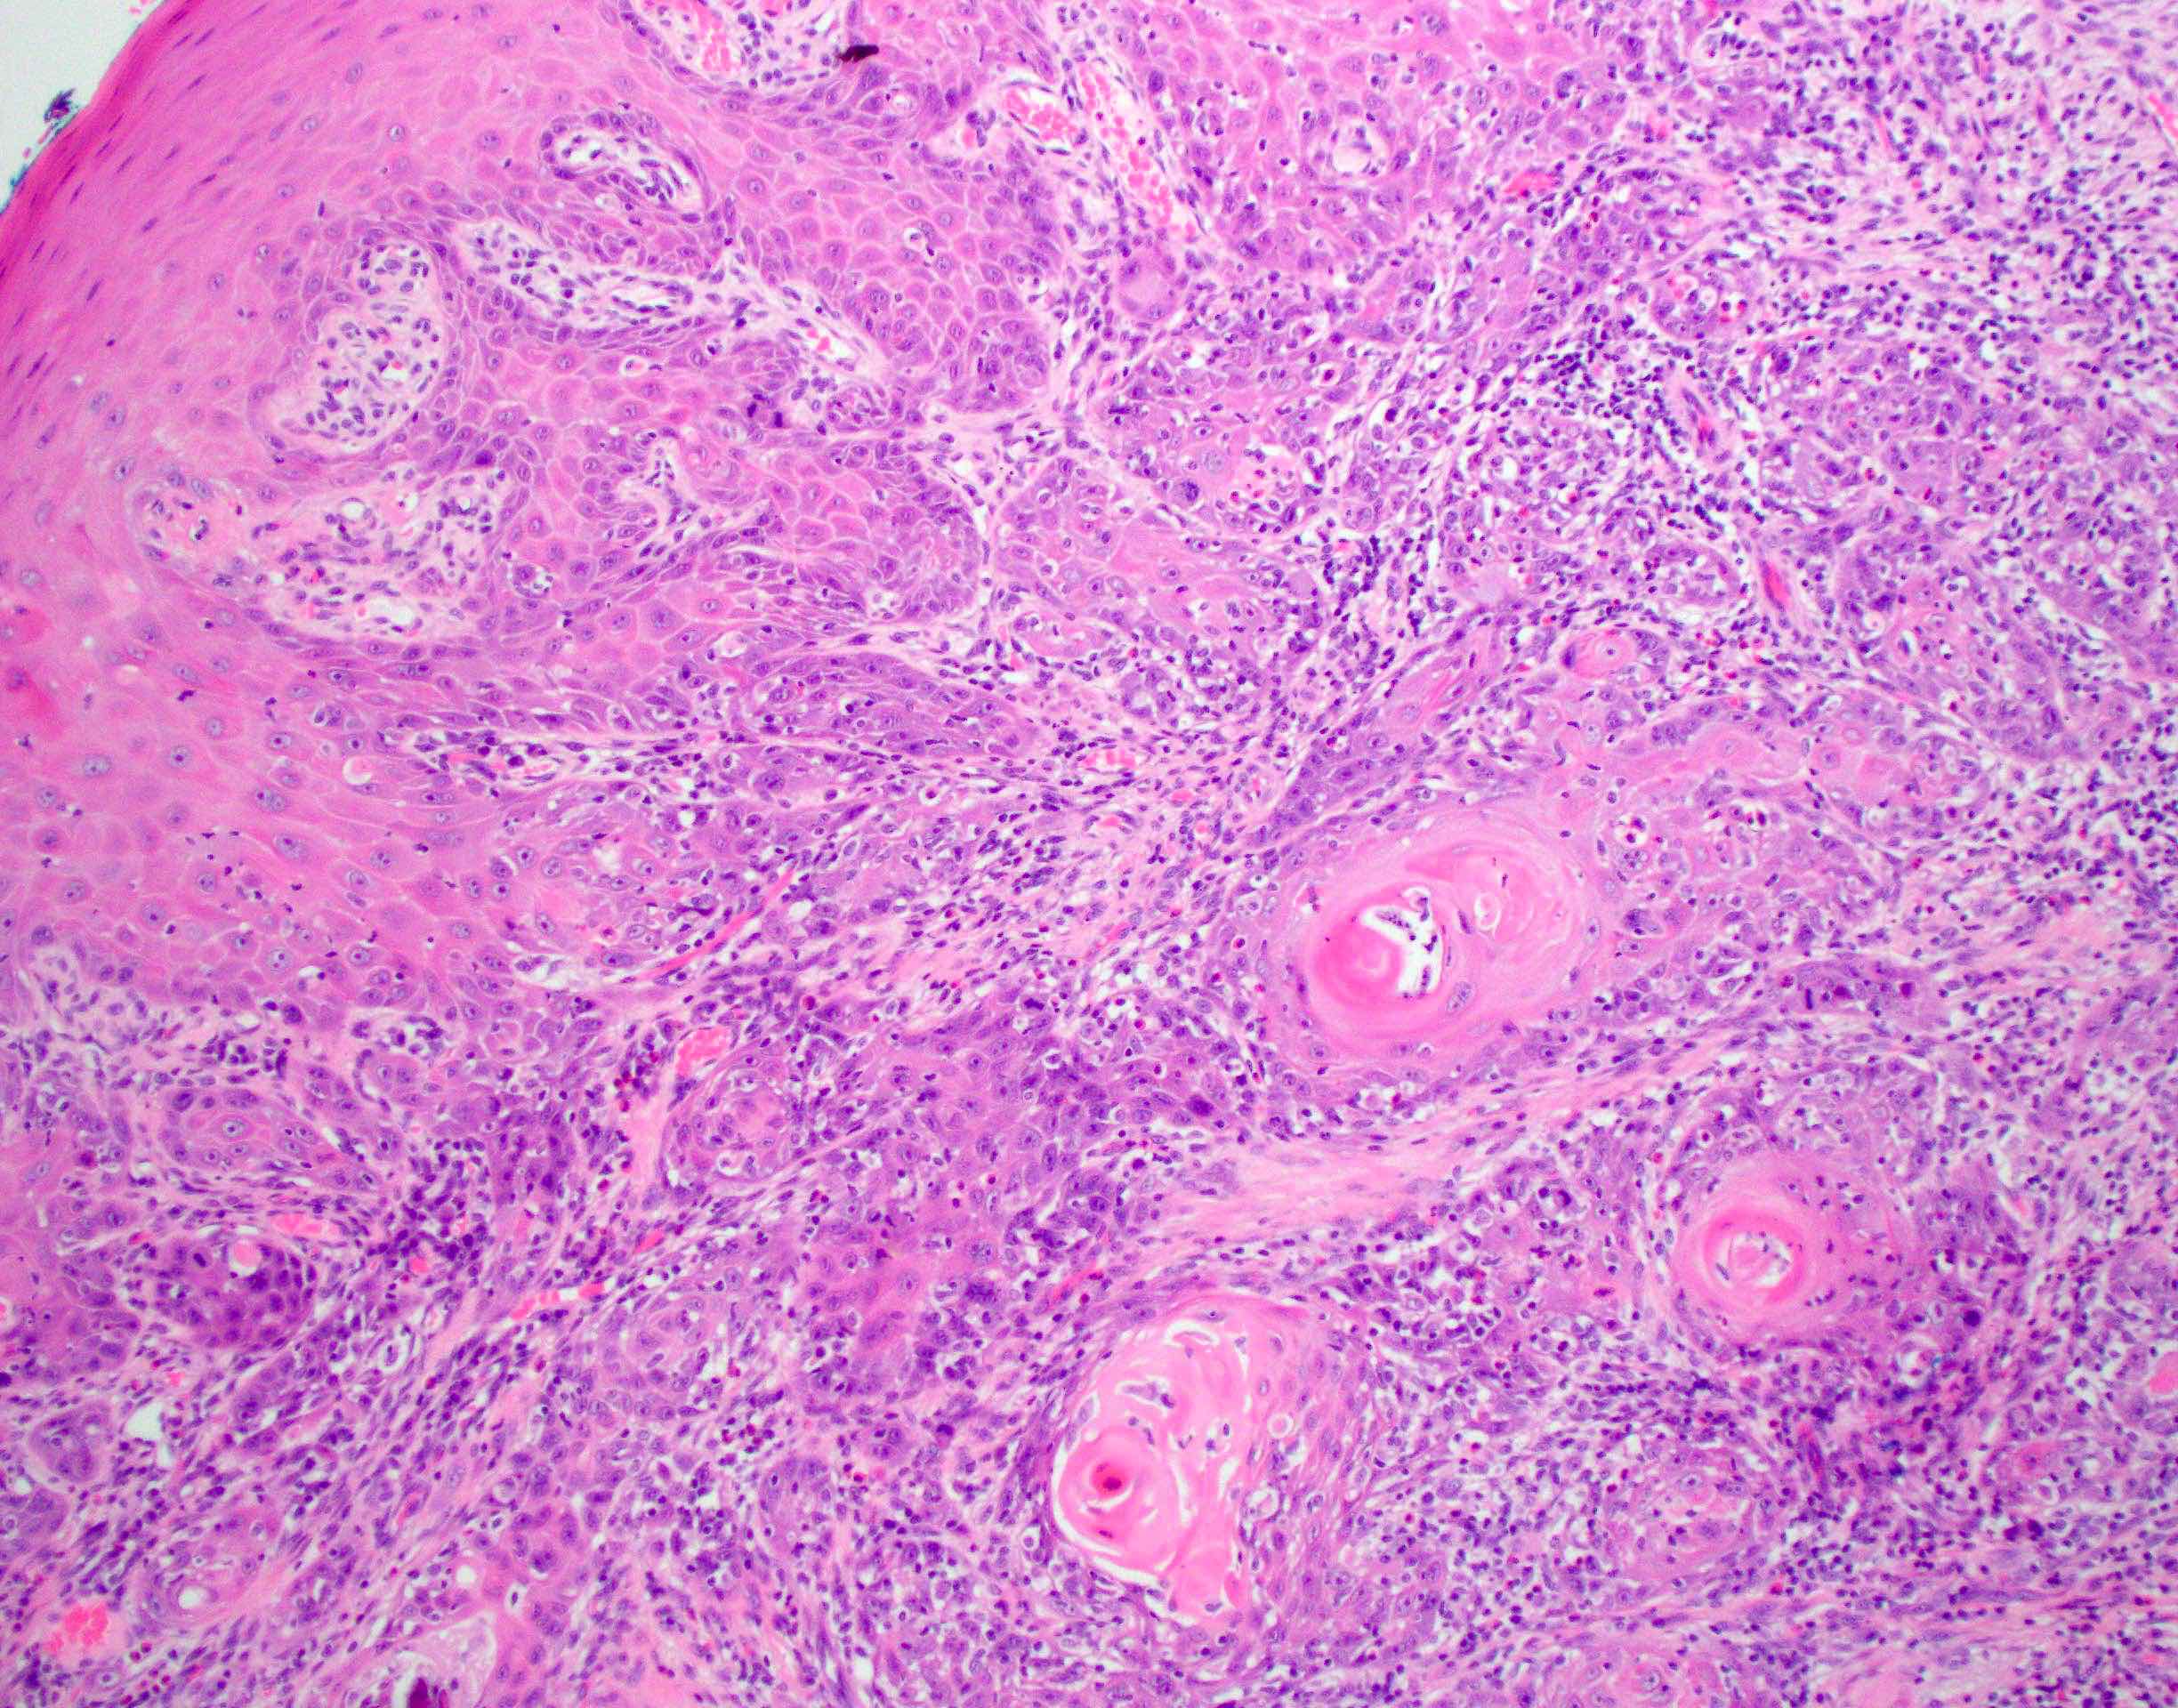

Microscopic (histologic) description

- Squamous cell carcinoma, conventional

- Most common and typical morphology of conventional keratinizing squamous cell carcinoma at any site

- Large polygonal malignant cells with intercellular bridges

- Cytoplasmic or extracellular eosinophilic keratin

- Dyskeratotic cells and squamous pearls

- Nuclear size, pleomorphism, hyperchromasia and mitoses increase with increasing grade

Microscopic (histologic) images

Contributed by Ruta Gupta, M.B.B.S., M.D.